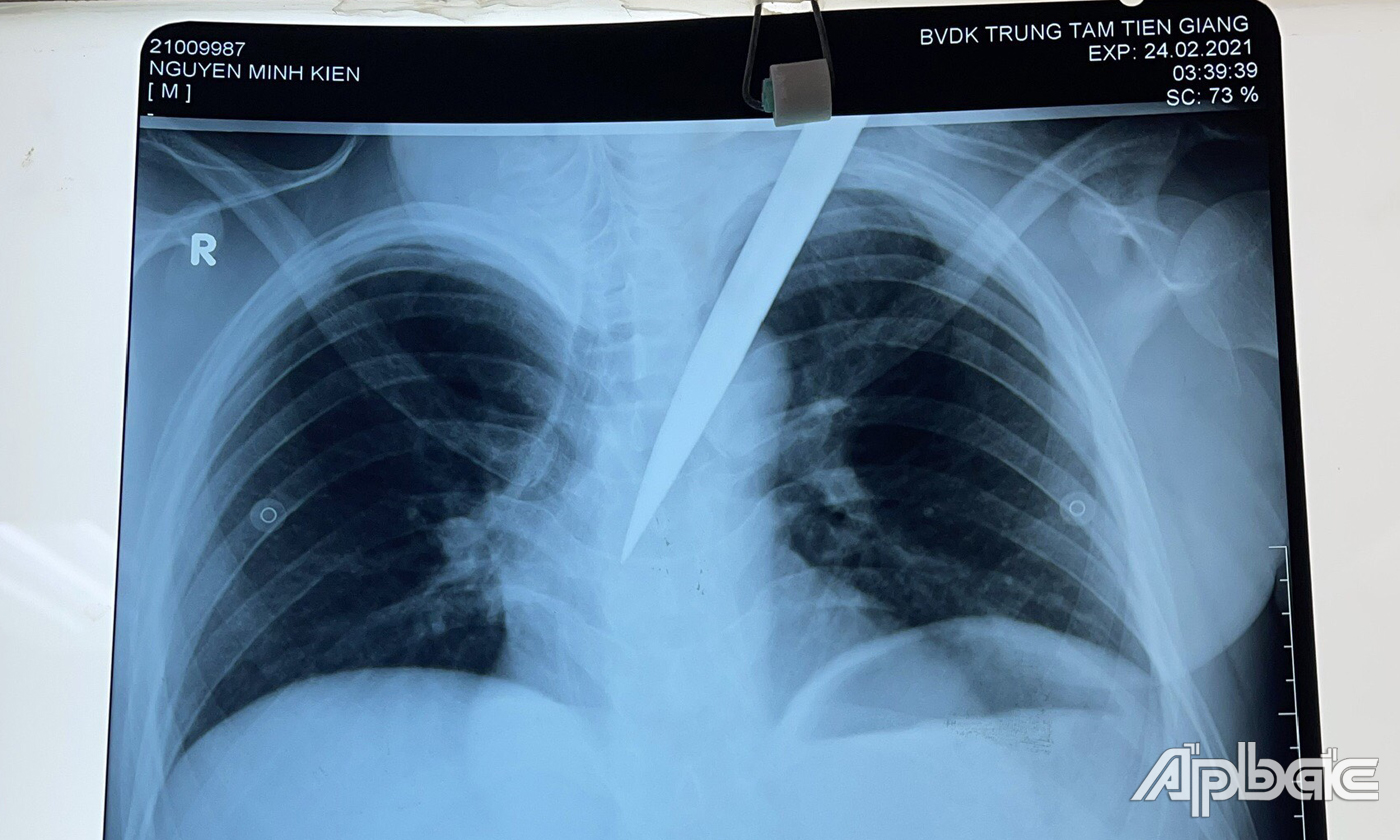

Phim X.Quang tình trạng của bệnh nhân K. khi nhập viện.